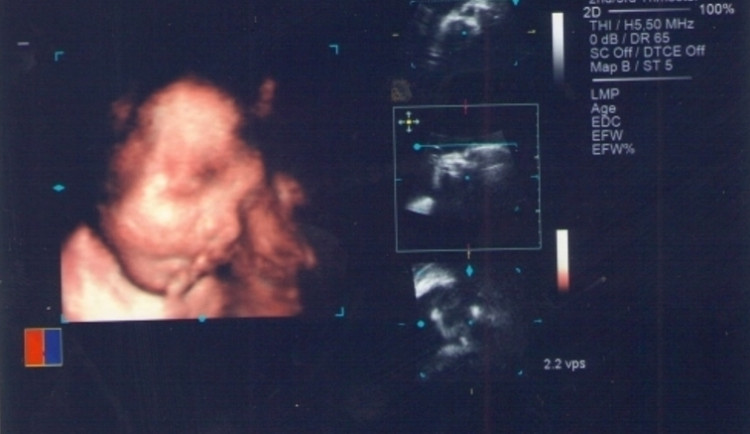

Kde že takový filmový trhák dávají?  V našem případě jsme se rozhodli , že si necháme tuto projekci promítnout v Centru lékařské genetiky, které sídlí v Českých Budějovicích.  O co v takovém trháku jde? Hlavní roli v něm má vaše miminko. Sledujete, jak si pěkně hoví v bříšku, různě pózuje nebo se schovává, jak vypadá, co dělá a to díky 3D ultrazvuku. Nejde o lékařské vyšetření na odhalení vývojových vad, ale opravdu jen o ,,rodinné video“.

Lépe strávený den jsem si snad ani nemohla přát. Asistentka se nám věnovala přes hodinu a byla neskutečně milá. Snažila se nám malého ukázat v celé jeho kráse, tak natáčela do různých pozic nejen mne, ale snažila se mírnými šťouchy natočit i našeho syna.  Celé pozorování miminka jsme sledovali na obrovské obrazovce, takže nám neunikly detaily jako prstíky, pusinka a ouška. A co bylo nejlepší? Celý filmový trhák jsme si odnesli domů na DVD, takže jsme se mohli s tímto zážitkem podělit s celou rodinou a přáteli. V ceně jsme měli i několik fotek, kterými jsme se mohli pyšnit na každém kroku. Z 3D ultrazvuky jsme odcházeli nadšeni a s krásným pocitem, že máme první ,,opravdovou“ fotografii našeho syna, a to za cca 1000kč opravdu stálo. Je to téměř nepopsatelný zážitek. Všem nastávajícím maminkám musím tento filmový trhák doporučit. Určitě z něj budete mít skvělý pocit  nejen vy,ale i vaše natěšené okolí!